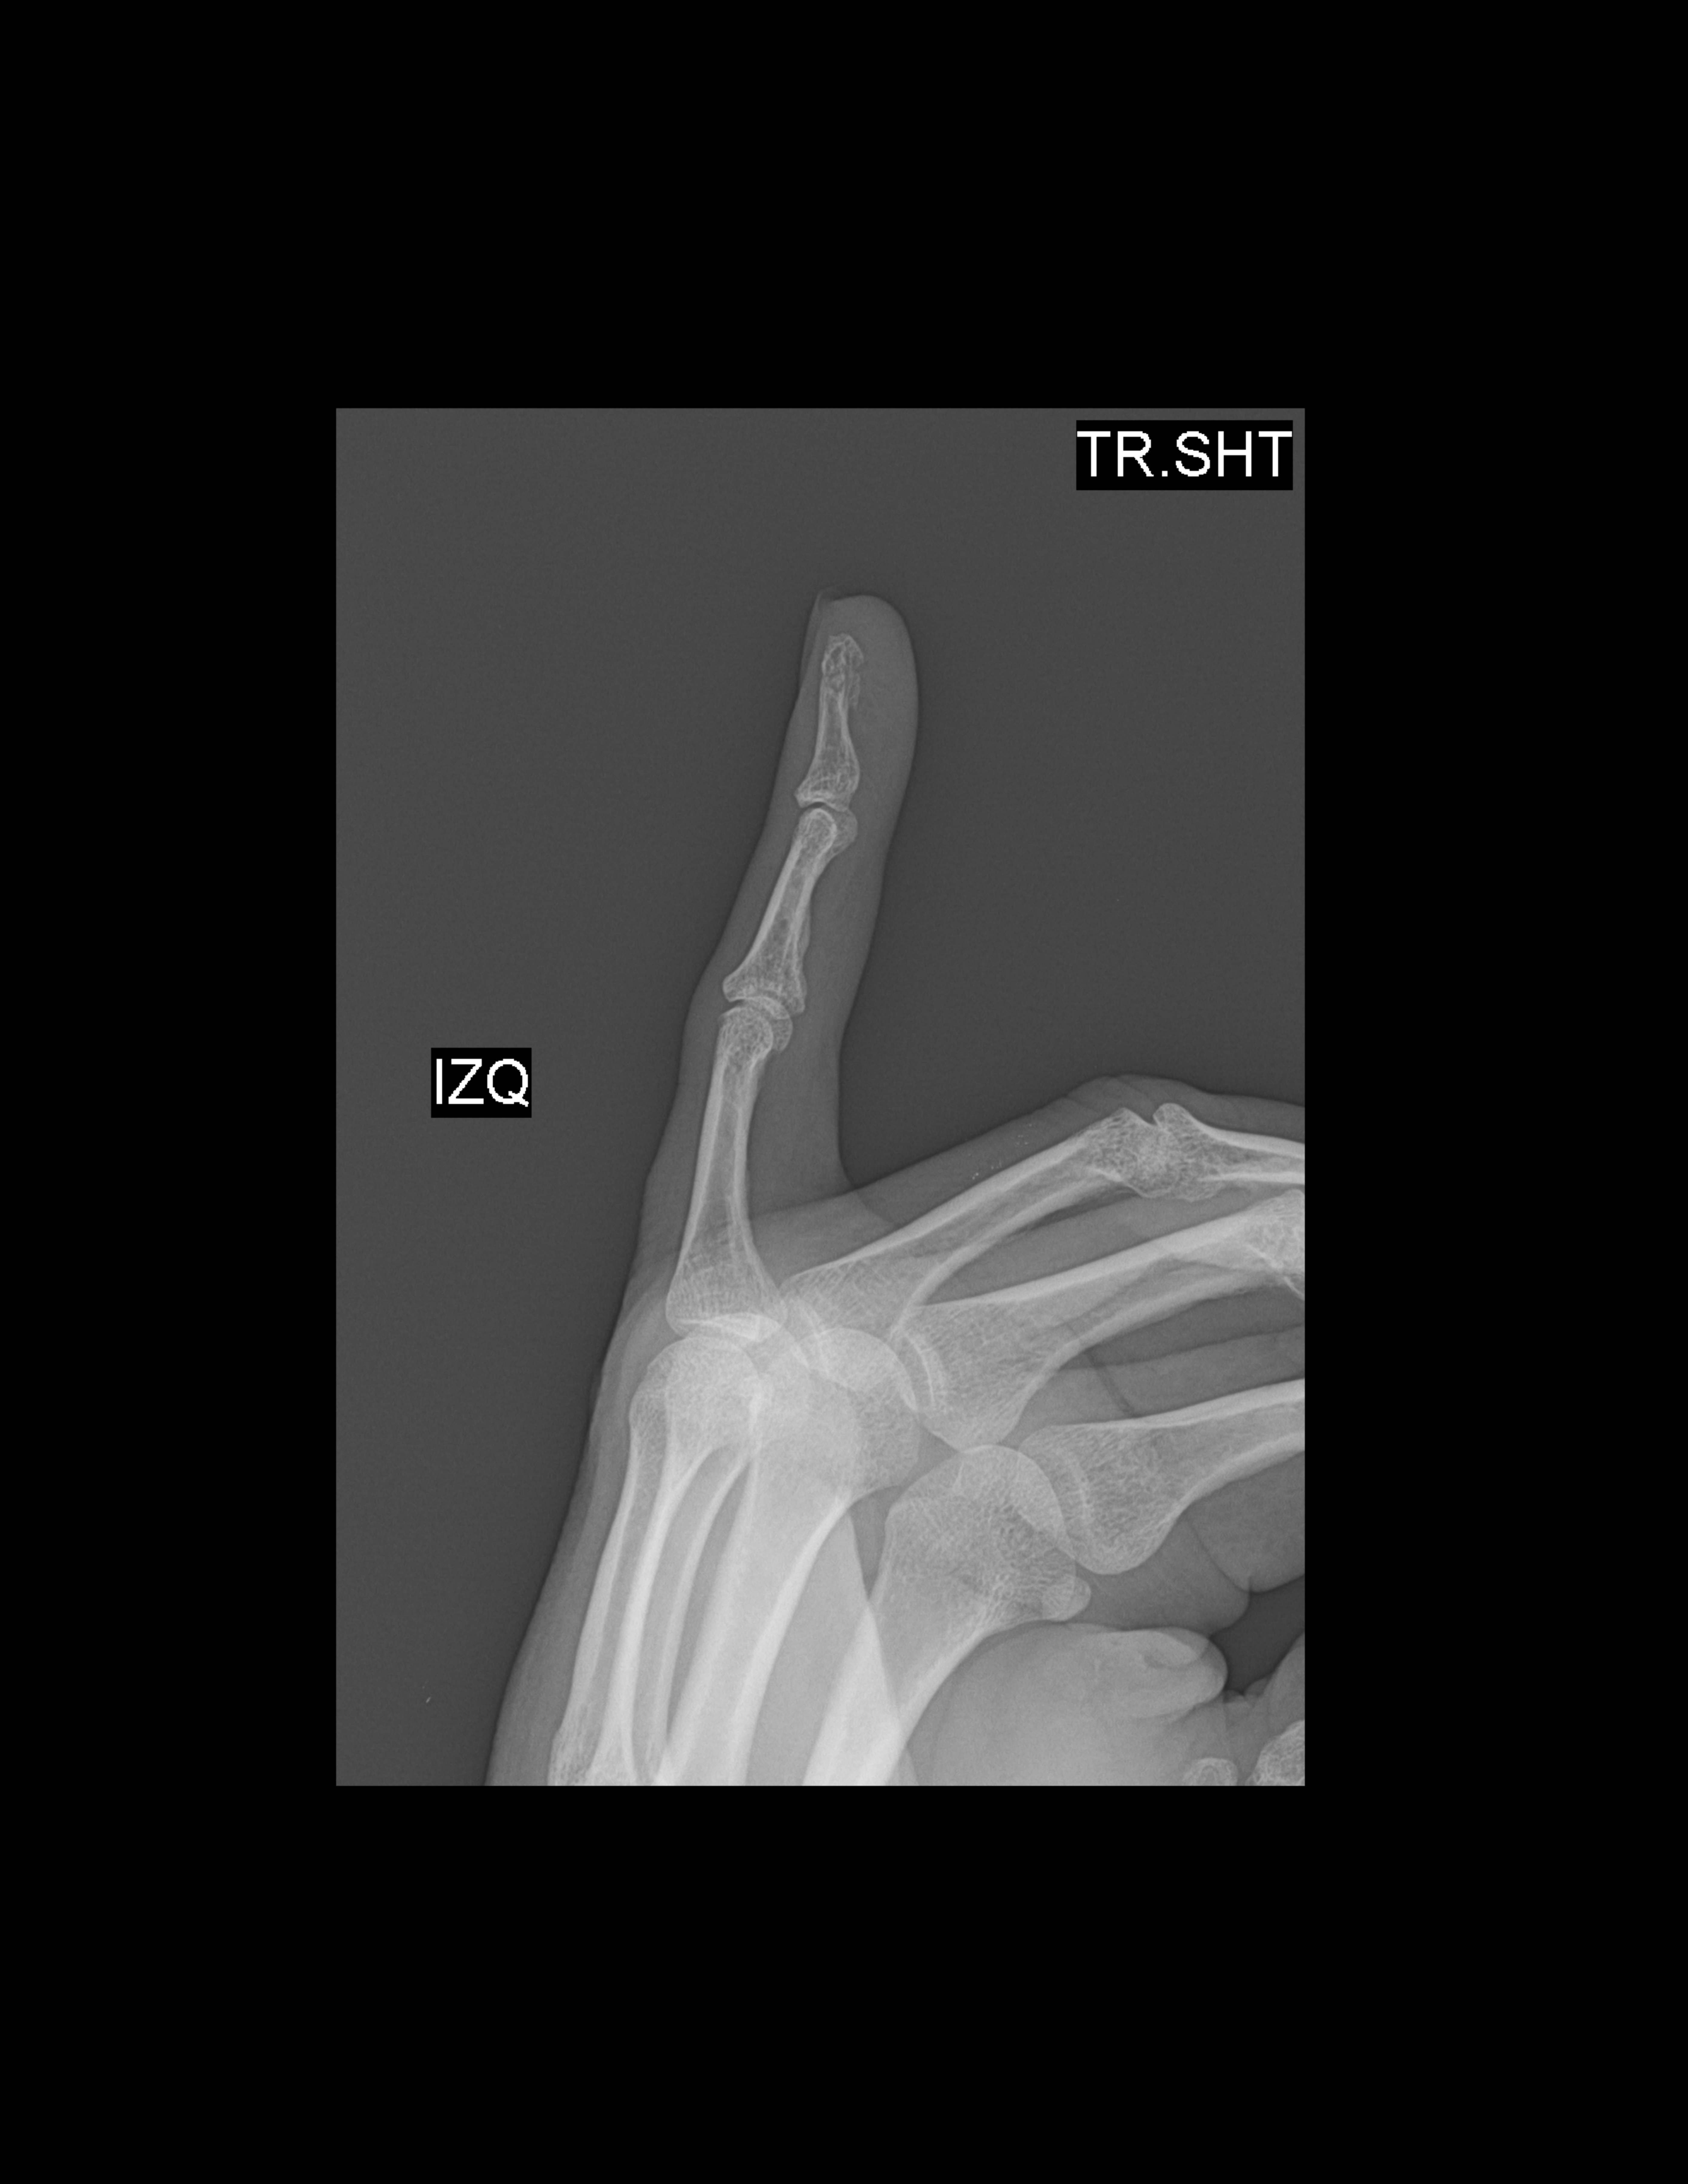

RADIOGRAFIAS AP Y LATERAL DE 5TO DEDO

Hallazgos:

-En lo observado de metacarpos, sin evidencia de lesiones blásticas, líticas o perdidas de la contigüidad.

-En lo observado de falanges, a nivel de falange distal a nivel de cabeza, con pérdida de la contigüidad por múltiples trazos, con leve desplazamiento. Resto sin evidencia de lesiones líticas, blásticas o perdida de la contigüidad.

-En lo observado de articulaciones metacarpofalángicas e interfalángicas, con amplitud respetada, sin evidencia de alteraciones.

-Tejidos blandos, con aumento del grosor y densidad de tejidos blandos periféricos al 5to dedo, a nivel de falange distal.

OPINIÓN RADIOLÓGICA:

EN EL PRESENTE ESTUDIO RADIOGRÁFICO, CON PRESENCIA DE FRACTURA POR MÚLTIPLES FRAGMENTOS A NIVEL DE CABEZA DE FALANGE DISTAL DEL 5TO DEDO, CON EDEMA ASOCIADO.